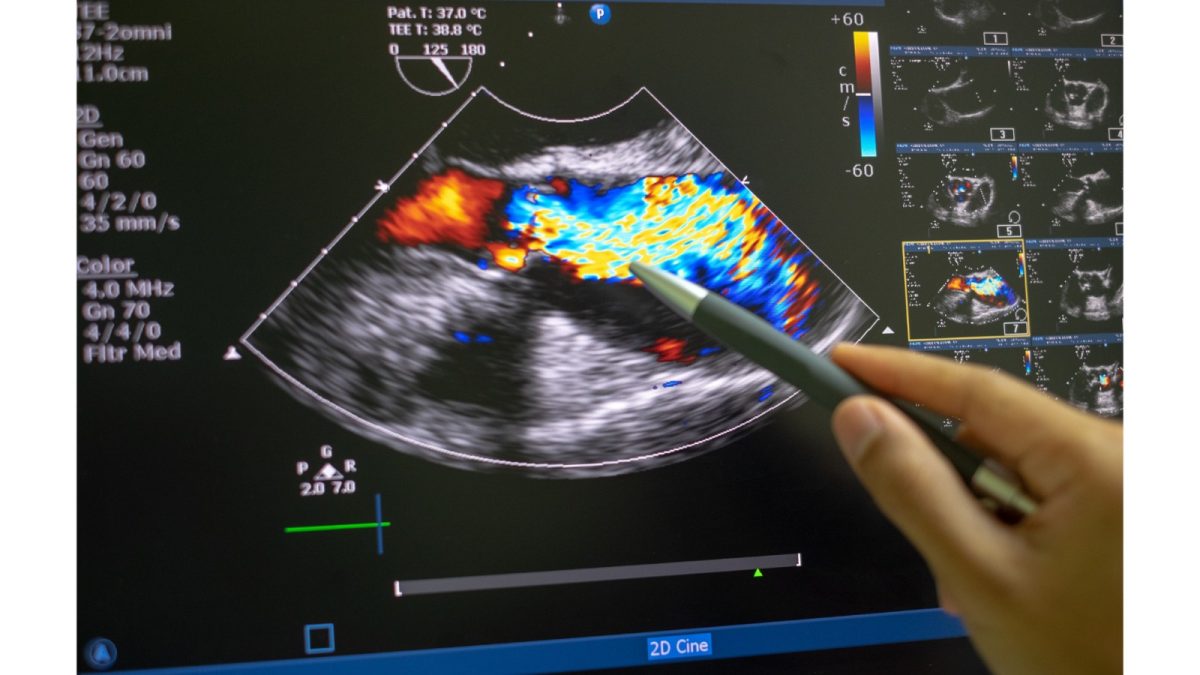

eco Doppler

Bolile venoase și arteriale la nivelul membrelor inferioare: cum te ajută eco Doppler în diagnostic și tratament

Ce este și cum funcționează eco Doppler?

Eco Doppler vascular este o metodă non-invazivă de imagistică ce evaluează circulația sângelui în artere și vene. Prin ultrasunete, oferă informații precise despre:

• Obstrucții sau îngustări vasculare

• Prezența cheagurilor de sânge

• Insuficiență sau reflux venos

• Calitatea fluxului sanguin

Este o investigație nedureroasă, fără radiații, sigură și potrivită pentru monitorizare repetată.